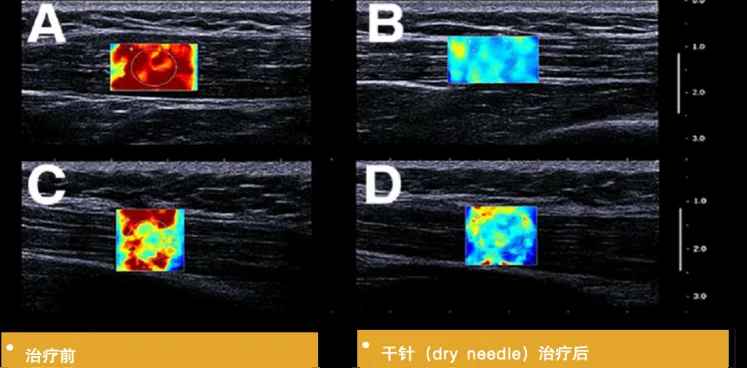

评估治疗效果:

可提供 MTrPs及其正常周围组织的客观指标,为 MPS的疗效评价提供客观依据。如果治疗有效,MTrPs处的硬度会降低,弹性会增加,RTSWE?技术可以通过治疗前后的颜色以及具体数值来对硬度进行对比。王墉琦[3]等利用针刺对腰臀肌筋膜疼痛综合征的治疗研究,证实了超声引导下针刺MTrPs的疗效,也表明弹性模量、杨氏模量及MTrPs与正常组织的应变比(SR)是超声检查的有效客观评价指标。RTSWE?引导的治疗能够有效减轻患者的疼痛,并改善肌肉的弹性。

640 (4).jpg

针刺治疗前后MTrPs点的E成像评估

(A、B坐位,C、D俯卧位)